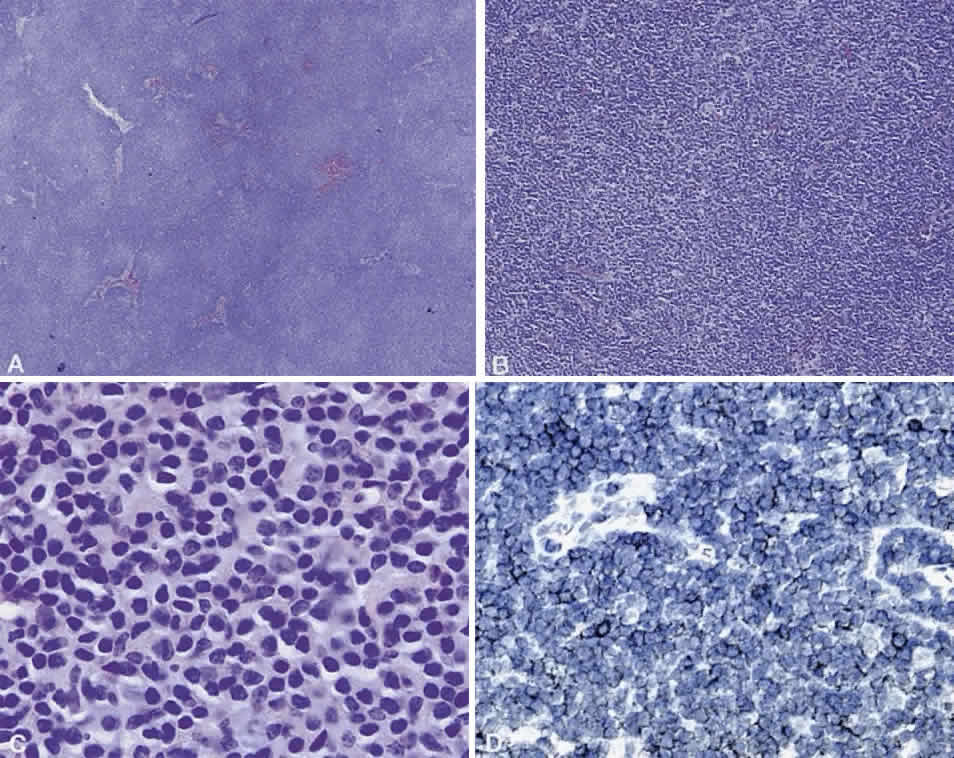

Numerous attempts have been made to classify lymphoid processes for clinical management and prediction of prognosis. Early classifications included only disease localized to the lymph node, which made classification of extranodal disease difficult and inaccurate. The Rappaport classification, first developed in 1956 and then modified in 1978, attempted to categorize lymphomas in two ways, first, using cytologic characteristics identified by conventional stains, and second, distinguishing between the follicular and diffuse growth pattern histologically38,39 (Table 3). The distinction of nodular, or follicular, and diffuse growth was considered useful because of the generally indolent nature of follicular growth, in which the tumor cell aggregates resemble germinal centers and disrupt the normal architecture of the node, compared with the appearance of diffuse growth, in which the lymph node is completely obliterated by a dense monotonous sheet of lymphocytes. In subsequent years, however, it was found that the descriptive growth pattern and cytogenetic characteristics of the Rappaport system did not predict prognosis reliably and were biologically inaccurate. The complexity of correlating degrees of differentiation, mitotic activity, and cytologic characteristics to prognosis have made lymphomas difficult to classify and have led to subsequent systems. The second system, proposed by Lukes-Collins in 1974, classifies lymphoma histologically according to its normal counterpart B-cell, T-cell, or null cell origin40,41 (see Table 3). Histologically, cells may appear small cleaved, large cleaved, small noncleaved, or large noncleaved, depending on the stage of B-cell arrest during normal transformation to immunoblast. Ninety percent of lymphomas are of B-cell origin, and the null cell also usually is of B-cell origin, although 10% may originate from T cells or histiocytes.42,43 Burkitt's lymphoma, the only lymphoma common in children, is a B-cell variant with a background of reactive histiocytes. As a result of histologic classification by Lukes-Collins, 76% of histiocytic lymphomas according to the Rappaport system were found to be not of histiocytic origin but of lymphocytic origin.40,44 The third system, the Working Formulation devised by the National Cancer Institute in 1982, attempted to predict prognosis by grouping lymphoma according to natural history, response to therapy, and overall survival.45 Three broad categories were established in terms of 5-year survival rates, the low-grade with a 50% to 70% survival rate, intermediate with 35% to 45%, and high grade with 23% to 32% (see Table 3). Orbital reactive hyperplasia, a relatively low-grade lesion, can be associated with systemic disease, whereas malignant or high-grade orbital lymphomas may be isolated findings. The Ann Arbor Staging Classification for Hodgkin's and non-Hodgkin's lymphomas was developed to stage disease based on systemic areas of involvement as a means of establishing a baseline for treating disease and following clinical progression46 (Table 4). Histologic classification, however, has been recognized as more useful than localization in the clinical management of nonHodgkin's lymphoma.47

While the Lukes-Collins and Working Formulation classifications were in wide use in the United States, the European literature made references to the Kiel and updated Kiel classifications, which led to disparities in classifying lymphoma. Another classification proposed by Jakobiec and coworkers was the most comprehensive classification available for orbital disease but failed to integrate systemic lymphoma, which is known to be associated in approximately half of cases.1 The most recent classification has made the system universal, comprehensive, and useful to interdisciplinary teams that characteristically manage patients with lymphoma. The International Lymphoma Study Group in 1994 developed the Revised European-American Lymphoma (REAL) classification (Table 5), which classifies lymphoid disease by the cell of origin into B-cell, T-cell, and natural killer cell lymphomas, leukemias, myeloma, and variants of Hodgkin's disease26 (Fig. 4). The identification of the putative benign progenitor cells has been inferred through the use of cell marker studies. The results of molecular genetic studies to identify immunoglobulin gene rearrangements and cytogenetic studies to detect chromosomal translocations in monoclonal proliferations have also been incorporated. A significant contribution of the REAL classification has been to incorporate primary extranodal lymphomas as recognizable and classifiable entities. As a result, new variants in this list include lymphoplasmacytic lymphoma, mantle cell lymphoma, marginal zone B-cell lymphoma, particularly mucosal-associated lymphoid tissue (MALT) lymphoma, subclasses of large cell lymphoma, and the natural killer cell lymphomas. Comparisons of the REAL classification to the Working Formulation and the Kiel classification are shown in Tables 6 and 7, respectively.48 The first series of 112 orbital lymphomas using the REAL classification reported the accuracy and utility of the system in classifying orbital lesions and predicting prognosis in combination with currently available immunophenotyping and immunocytogenetic studies.49 The REAL classification does not classify disease based on the degree of differentiation or clinical prognosis. However, a proposed prognostic scheme has been developed in accordance with the REAL classification28 (Table 8). In this text, tumor nomenclature adheres as strictly as possible to the REAL classification.